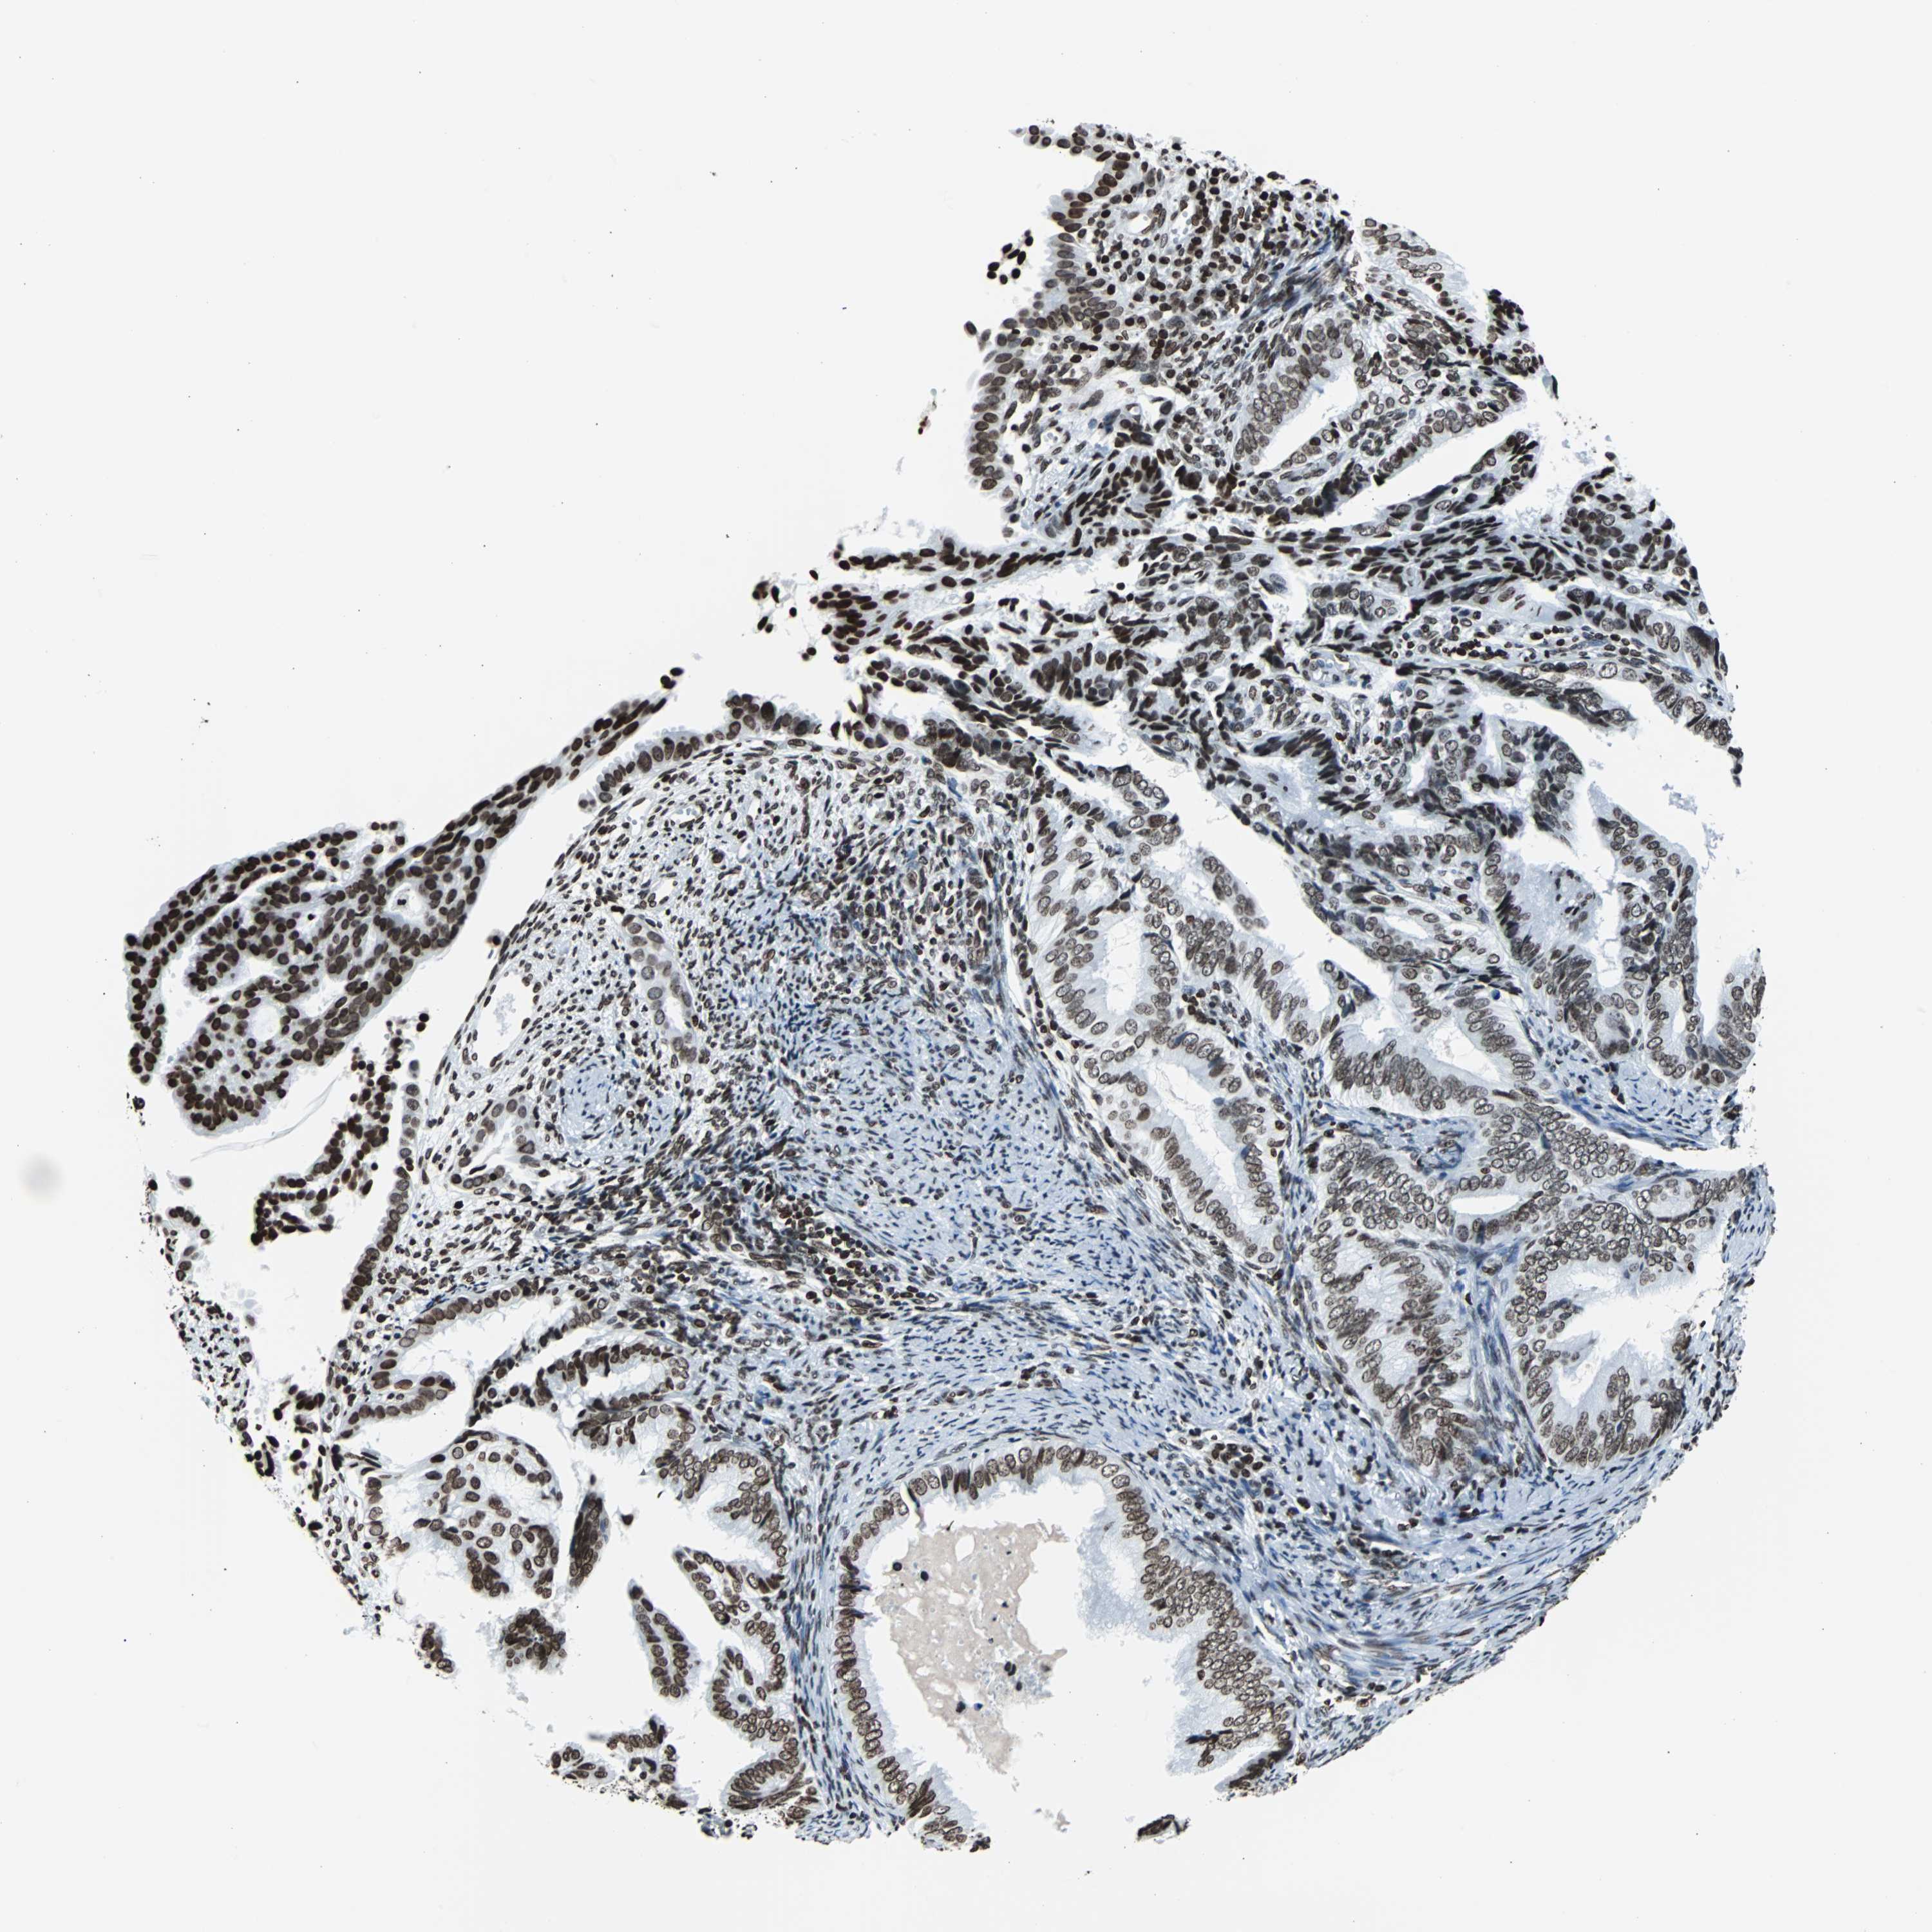

ENDOMETRIAL CANCER - Protein expressioni

A mouse-over function shows sample information and annotation data. Click on an image to view it in a full screen mode. Samples can be filtered based on level of antibody staining by selecting one or several of the following categories: high, medium, low and not detected. The assay and annotation is described here.

Note that samples used for immunohistochemistry by the Human Protein Atlas do not correspond to samples in the TCGA dataset.

Antibody stainingi

Antibody staining in the annotated cell types in the current human tissue is reported as not detected, low, medium, or high, based on conventional immunohistochemistry profiling in selected tissues. This score is based on the combination of the staining intensity and fraction of stained cells.

Each image is clickable and will lead to virtual microscopy that enables deeper exploration of all samples and also displays staining intensity scores, fraction scores and subcellular localization as well as patient and tissue information for each sample.

Antibody HPA042205

Antibody HPA043013

Antibody HPA048671

Antibody CAB007814

Staining

High

Medium

Low

Not detected

Intensity

Strong

Moderate

Weak

Negative

Quantity

>75%

75%-25%

<25%

None

Location

Nuclear

Cytoplasmic/membranous

Cytoplasmic/membranous,nuclear

Adenocarcinoma, NOS